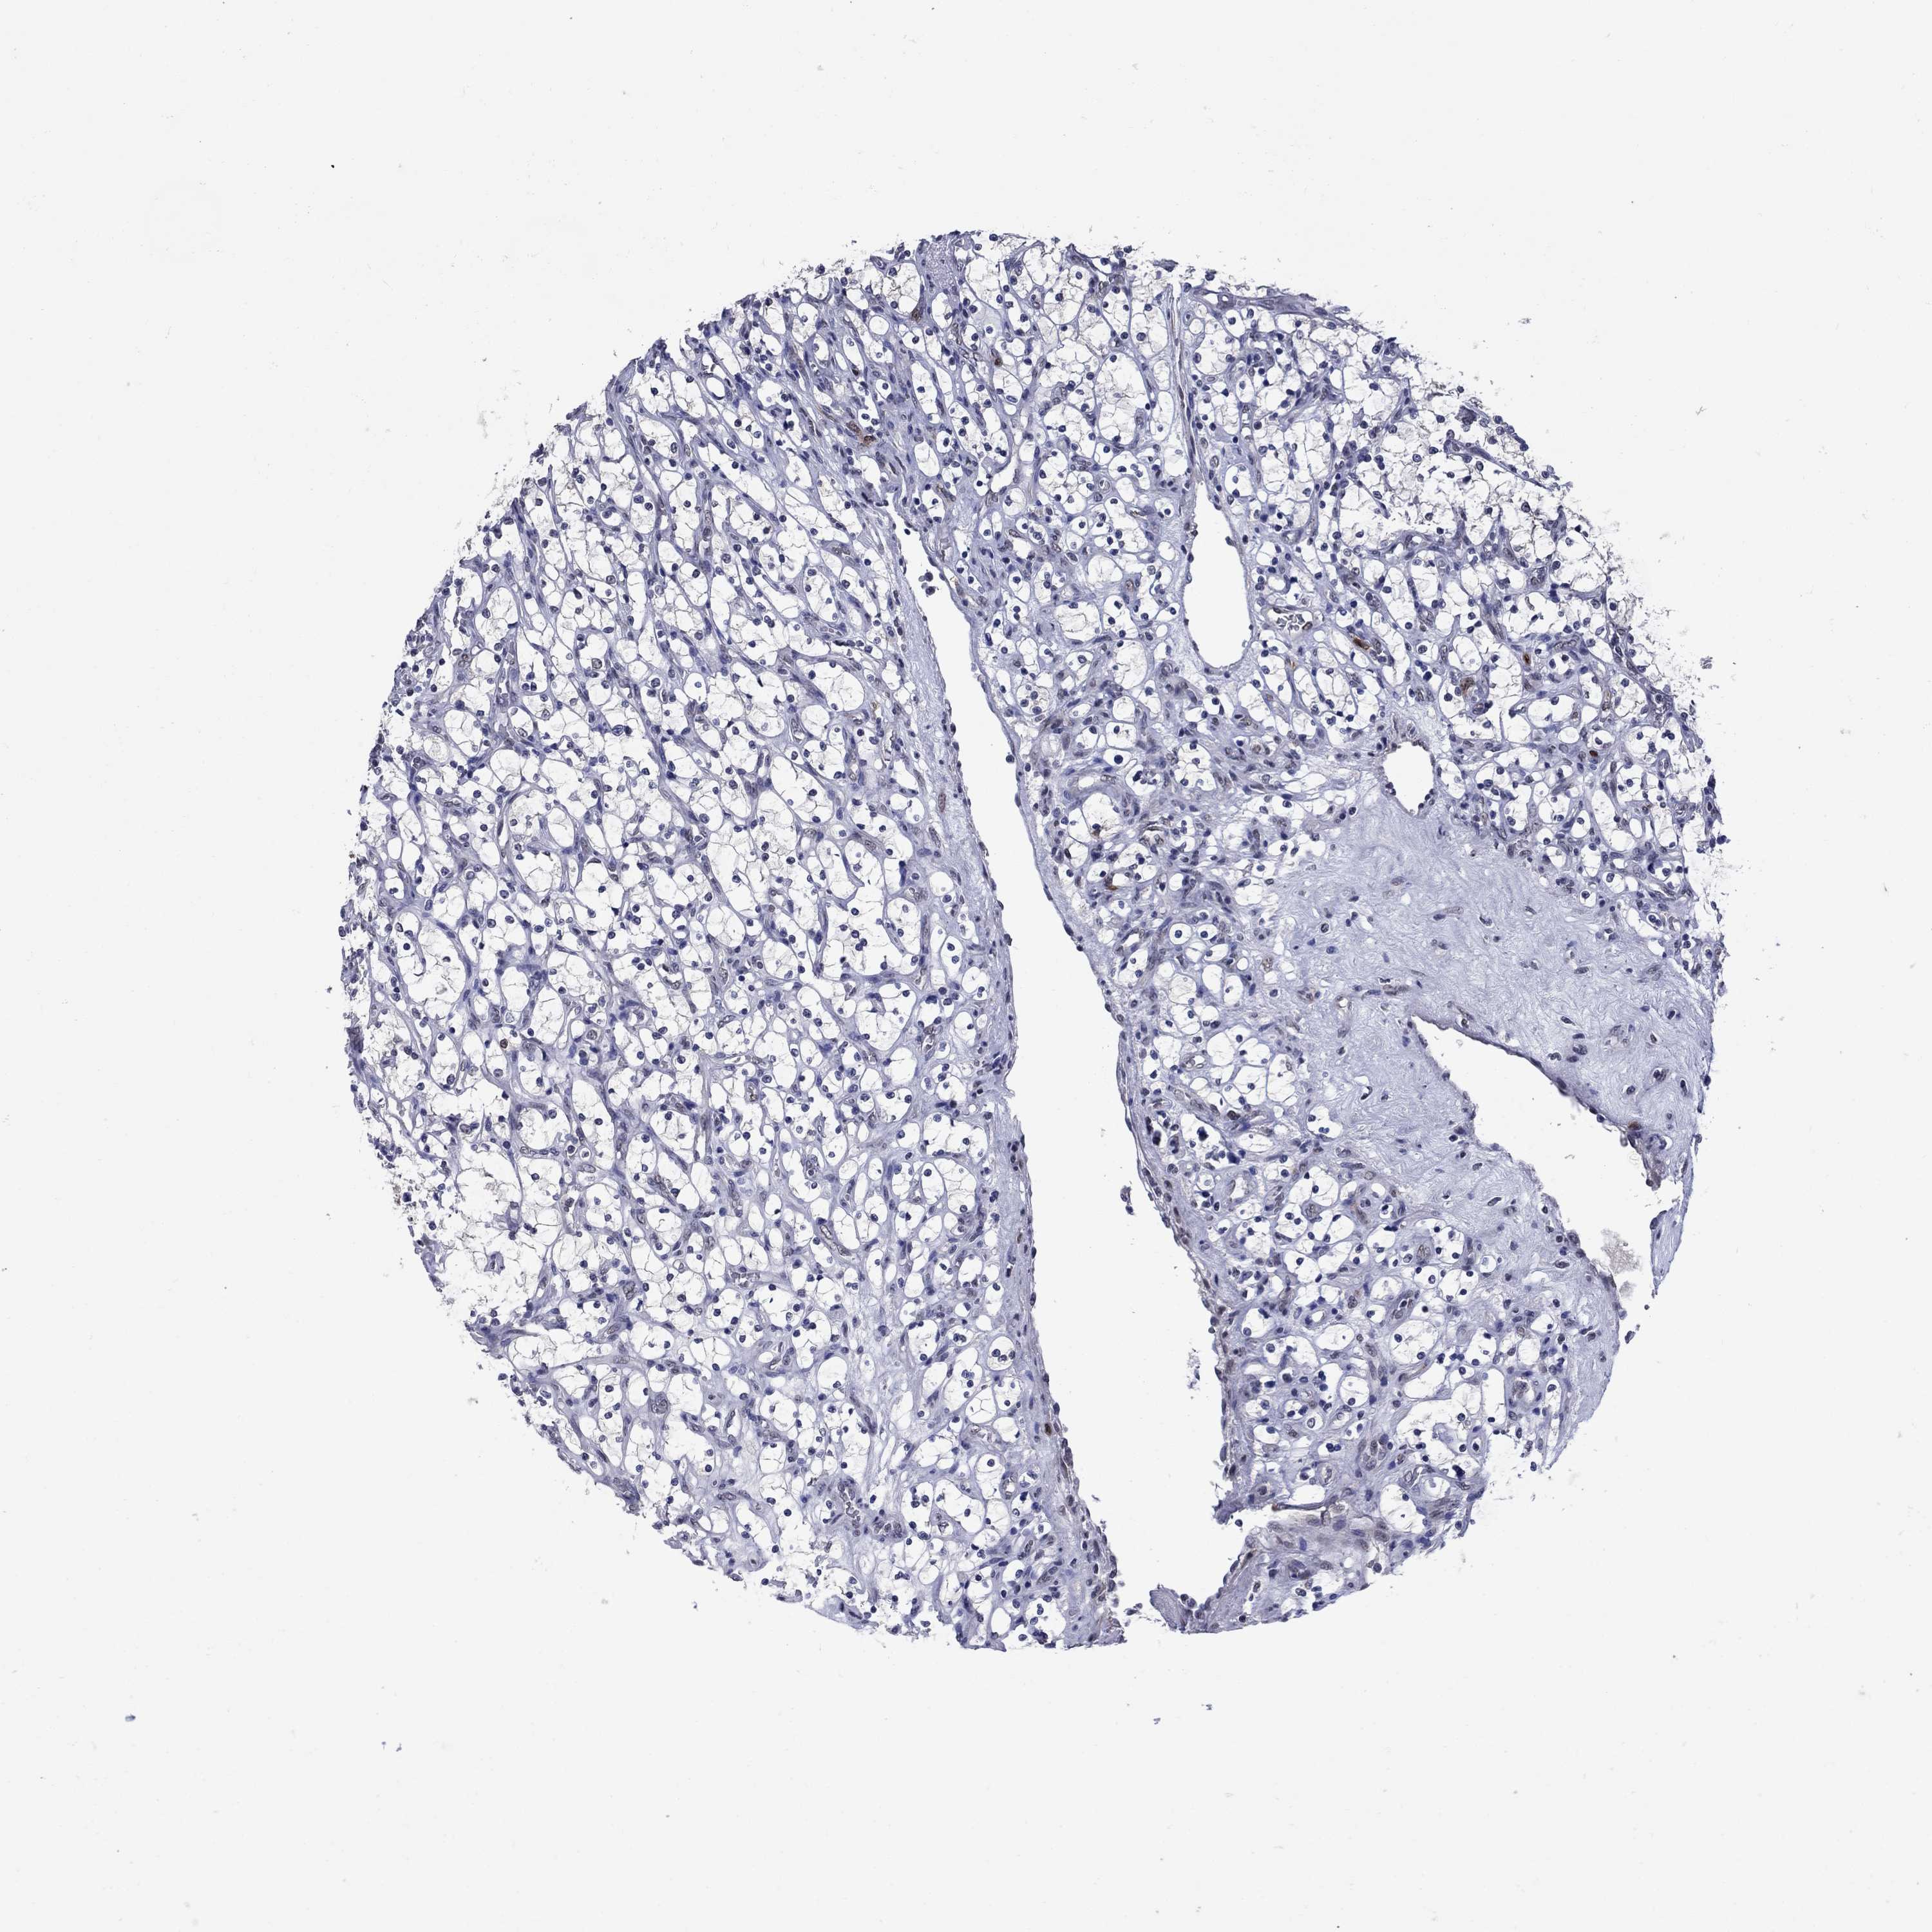

KIDNEY RENAL CLEAR CELL CARCINOMA (VALIDATION) - Interactive survival scatter ploti

The Survival Scatter plot shows the clinical status (i.e. dead or alive) for all individuals in the patient cohort, based on the same data that underlies the corresponding Kaplan-Meier plots. Patients that are alive at last time for follow-up are shown in blue and patients who have died during the study are shown in red.

The x-axis shows the expression levels (FPKM) of the investigated gene in the tumor tissue at the time of diagnosis. The y-axis shows the follow-up time after diagnosis (years). Both axes are complimented with kernel density curves demonstrating the data density over the axes. The top density plot shows the expression levels (FPKM) distribution among dead (red) and alive patients (blue). The right density plot shows the data density of the survived years of dead patients with high and low expression levels respectively, stratified using the cutoff indicated by the vertical dashed line through the Survival Scatter plot. This cutoff is automatically defined based on the FPKM cutoff that minimizes the p-score. The cutoff can be changed by dragging the vertical line or by entering a cutoff value in the square labeled "Current cut-off".

Under the Survival Scatter plot the p-score landscape (black curve; left axis) is shown together with dead median separation (red curve; right axis). Dead median separation is the difference in median mRNA expression between patients who have died with high and low expression, respectively. It is calculated as follows: median FPKM expression of dead patients with high expression - median FPKM expression of dead patients with low expression. This is intended to aid the user in visually exploring custom cutoffs and the associated p-scores and dead median separation.

Individual patient data is displayed and can be filtered by clicking on one or more of the category buttons on the top of the page. Categories describing expression level and patient information include: high, low, alive, dead, female, male and tumor stages. The scale of the x-axis can be toggled between linear and log-scale by clicking on the "x log" button. Mouse-over function shows TCGA ID, patient information and mRNA expression (FPKM) for each patient.

& Survival analysisi

Kaplan-Meier plots summarize results from analysis of correlation between mRNA expression level and patient survival. Patients were divided based on level of expression into one of the two groups "low" (under cut off) or "high" (over cut off). X-axis shows time for survival (years) and y-axis shows the probability of survival, where 1.0 corresponds to 100 percent.

TYMS is not prognostic in Kidney Renal Clear Cell Carcinoma (validation)

Best expression cut offi

Based on the FPKM value of each gene, patients were classified into two groups and association between prognosis (survival) and gene expression (FPKM) was examined. The best expression cut-off refers the FPKM value that yields maximal difference with regard to survival between the two groups at the lowest log-rank P-value. Best expression cut-off was selected based on survival analysis .

When clicking on this number, the vertical dashed line indicating cut-off, the interactive survival plot, and the Kaplan-Meier curve will be adjusted to show results based on the best expression cut-off.

: 29.12

P scorei

Log-rank P value for Kaplan-Meier plot showing results from analysis of correlation between mRNA expression level and patient survival.

N/A

5-year survival highi

5-year survival for patients with higher expression than the expression cutoff.

For melanoma and glioma, 3-year survival is shown.

5-year survival lowi

5-year survival for patients with lower expression than the expression cutoff.

TCGA RNA samplesi

RNA-seq data is reported as average FPKM (number Fragments Per Kilobase of exon per Million reads), generated by the The Cancer Genome Atlas (TCGA) .

Normal distribution across the dataset is visualized with box plots, shown as median and 25th and 75th percentiles. Points are displayed as outliers if they are above or below 1.5 times the interquartile range. FPKM values of the individual samples are presented next to the box plot.

Average pTPM 44.7

Number of samples 100